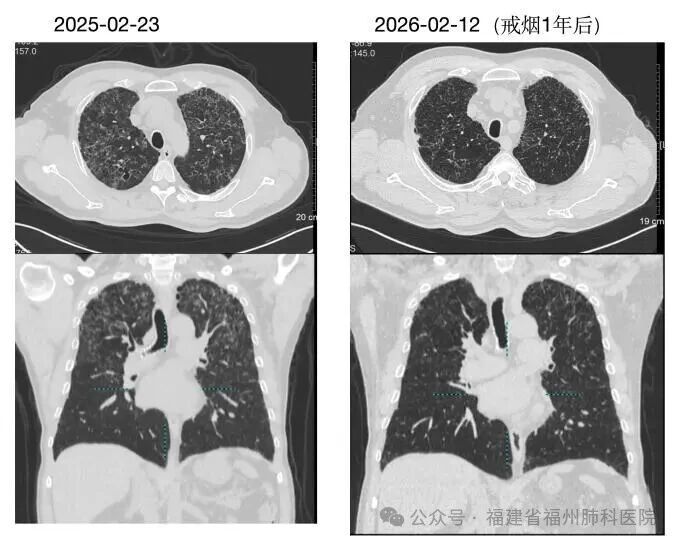

治疗关键只有一个对于PLCH患者,最重要的治疗是彻底戒烟。早期患者戒烟后病情可稳定甚至改善。如曾经在我院确诊PLCH的另一位患者刘先生,在彻底戒烟后复查肺部CT,病灶明显吸收(肺部CT对比如下图)。进展期可能需要激素或免疫治疗,极少数严重病例需考虑肺移植。